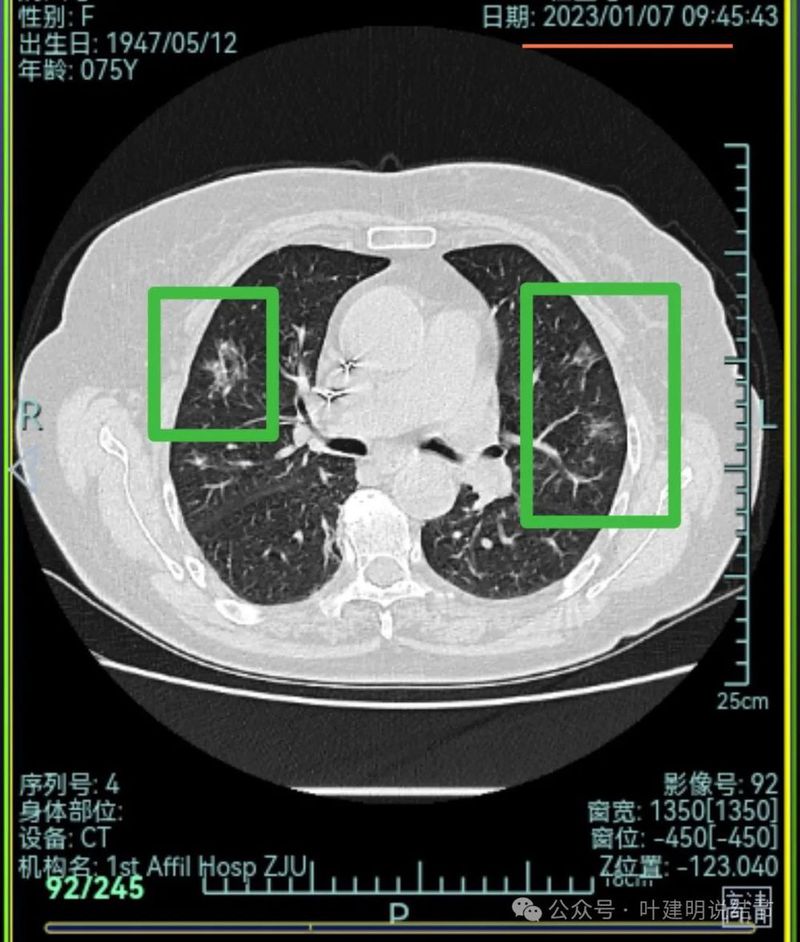

右上叶混合密度结节,有分叶征,内部密度杂乱,有毛刺征,灶内有空泡征,单处单灶看也是与恶性较为符合;左上叶两处磨玻璃阴影,轮廓稍糊,边界稍不清,感染稍倾向炎性些。

右下混合密度结节,有明显血管进入,轮廓较清,瘤肺边界较清,单灶单处看也像恶性些;

左下胸膜下混合密度结节,边缘不平有毛刺,但毛刺不是很锐利,与胸膜侧紧贴,没有明显牵拉。

右中叶混合密度结节,有血管进入,表面不平,略有胸膜牵拉,但感觉病灶显散,聚拢性不够。

右下叶磨玻璃结节,贴着叶间裂,缺乏收缩力,中间有小空泡,单灶单看恶性不能除外,但略倾向炎性点。

右中叶磨玻璃病灶,轮廓稍糊,瘤肺边界欠清,呈片状,与炎性更符合点。

当时影像考虑:

从上述两肺多发病灶来看,虽有多处也恶性的混合密度结节也是符合的,但由于病灶太多,有的轮廓与边界模糊,首次发现肯定要先考虑感染性病变,并依病毒感染予以治疗并适时复查。因为退一步讲,即使多原发肺癌是这个样子,近80岁的高龄,也肯定不能先考虑手术来解决,那是切不光的。